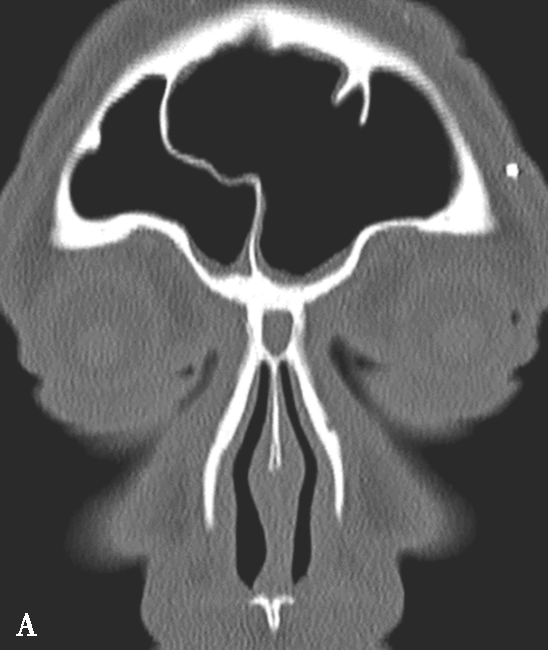

蝶窦气化可扩展到前窗突、翼突,分别称为前窗突气化、翼突气化,有时后床突、蝶骨小翼或鞍背也可气化,这些变异增加了损伤周围的重要结构(比如视神经管、翼管、圆孔等)的机会,术前应仔细地观察。

颈内动脉管突入蝶窦内,有时颈内动脉管壁可缺如,在行蝶窦手术时应注意此种情况,避免损伤造成严重的并发症,而这些变异只能根据CT来确定。

蝶窦常见解剖变异包括:①有分隔的蝶窦,可为纤维或骨性分隔分成几个不对称的部分,此变异容易导致蝶窦手术引流不完全而残留病变;②介甲型蝶窦,窦腔略有气化,发育很小,窦腔后缘与鞍结节垂直线之间尚有10mm厚骨质;③鞍前型蝶窦,蝶窦发育较小,窦腔后缘与鞍结节垂直线相齐,恰好位于蝶鞍之前,蝶鞍底大部分为松质骨;④半鞍型蝶窦,发育尚好,后上缘占鞍底前半部;⑤全鞍型蝶窦,发育良好,自鞍结节至鞍背连线的全鞍底与蝶窦只一层薄骨板;⑥枕鞍型蝶窦,与全鞍型相似,但发育更大,后缘超过鞍背垂线,蝶窦侵入枕骨使斜坡骨板更薄(图1-3-7)。

图1-3-7 蝶窦及蝶窦区解剖变异

A.颈内动脉管突入蝶窦;B.蝶窦间隔(白箭);C.左侧翼突气化;D.蝶嵴(星)、蝶骨大翼(白箭)、鞍背气化(虚箭);E.蝶骨小翼气化(白箭);F、G.鞍前型蝶窦(三角);H、I.甲介型蝶窦;J、K.鞍型蝶窦;L.Odoni气房(白箭)